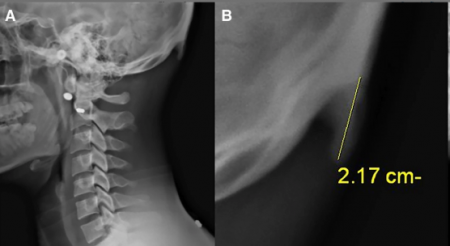

Исследование проведенное австралийскими учеными из University of the Sunshine Coast, Дэвидом Шахаром в 2016 году, показало, что из 218 обследованных пациентов 41% имеют костный нарост на черепе, связанный с длительным использованием смартфона. Другое исследование, проведённое в 2018 году, где обследовалось уже 1200 пациентов подтвердило эти выводы.

Исследование показало, что нарост чаще встречается у мужчин, чем у женщин, 67% против 20%. Самый длинный нарост в 35,7 мм был у мужчины и 25,5 мм у женщины. Больше всего подвержены этому изменению люди в возрасте от 18 до 30 лет (те кто чаще использует смартфон).

Это явление, получило название "текстовая шея", - это когда шея сильно напрягается, чтобы стабилизировать голову, в то время как голова направлена вниз для просмотра устройств, таких как смартфоны и планшеты. Такое положение головы становится дополнительной нагрузкой для мышц, соединяющих шею с затылком. В ответ на постоянное напряжение мышц, сухожилий и других соединительных тканей на черепе начинают формироваться новые выросты, которые расширяют площадь крепления мышц, обеспечивая им большую плотность и силу.